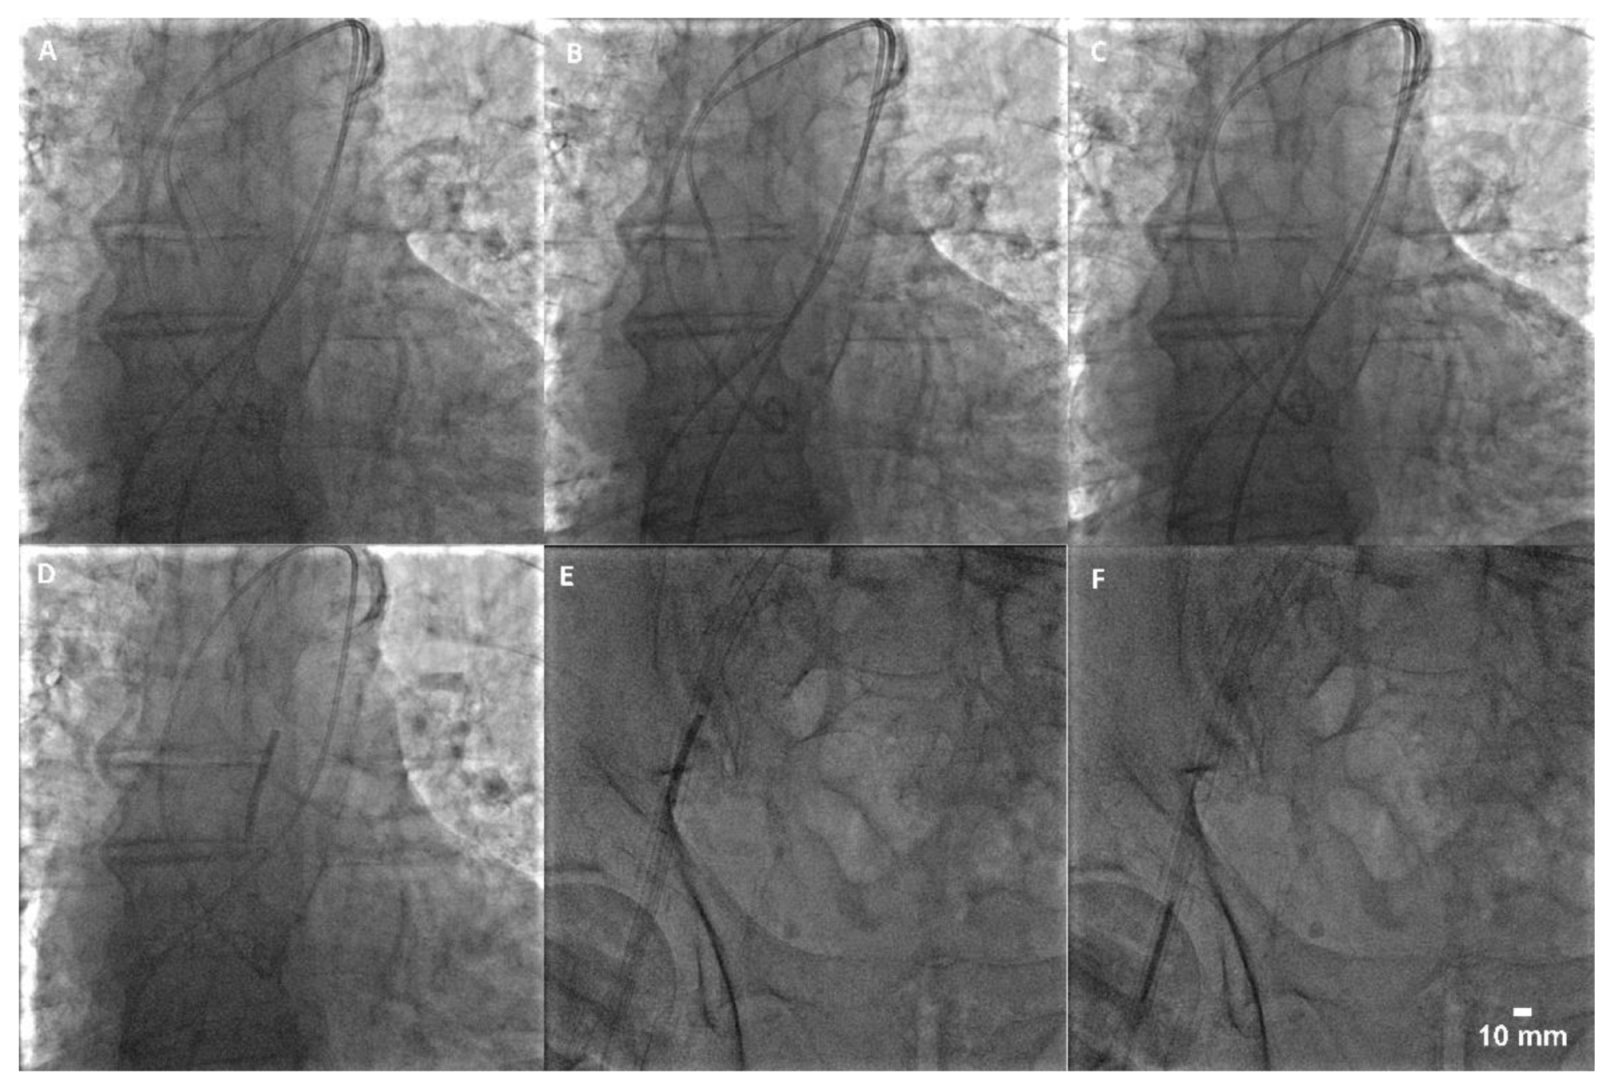

This satisfied the prerequisite for the Confida wire removal and the introduction of coronary guidewire BMW Universal (0.014”; Abbott™, Abbott Park, IL, USA) along with the rapid exchange balloon catheter SeQuent NEO (2.5 × 25 mm2; Bbraun™, Melsungen, Germany), which were placed over the severed sheath. The balloon was then inflated and slowly moved into the Medtronic Sentrant introducer sheath under the fluoroscopic guidance. The balloon was then deflated and together with the guidewire removed out of the sheath. This was followed by the introduction of the standard support J-wire (0.035″) and conjoint removal of the introducer sheath, AL2 catheter and the severed sheath (Figure 3). The introducer sheath was thereafter intersected to visualize the distal part of the severed femoral sheath (Figure 1).

Figure 3. Step-by-step recapture of the severed sheath: (A) wiring; (B) balloon crossing; (C) balloon capture; (D) balloon snaring (aorta); (E) balloon snaring (introducer sheath); (F) balloon deflation and evacuation.